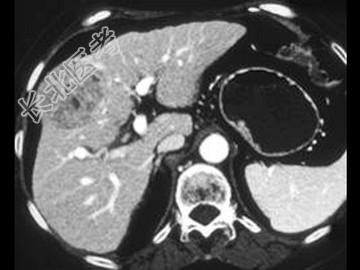

- 单项选择题女,55岁, 右上腹痛,消瘦乏力3月, 结合图像,最可能的诊断是 ( )

A、肝血管瘤

B、肝腺瘤

C、肝癌

D、肝脓肿

E、肝转移癌